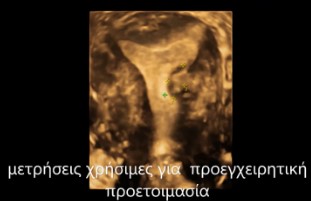

Παράδειγμα Υπερηχογραφικής σαλπιγγογραφίας HYFOSY βέλος : όπου φαίνεται διαπερατότητα, υπερηχογενές σκιαγραφικό στην αριστερή σάλπιγγα με ροή

HYFOSY 3D

Παράδειγμα Υπερηχογραφικής σαλπιγγογραφίας HYFOSY με τρισδιάστατη απεικόνιση ενδομητρικής κοιλότητας και σαλπιγγικής διαπερατότητας